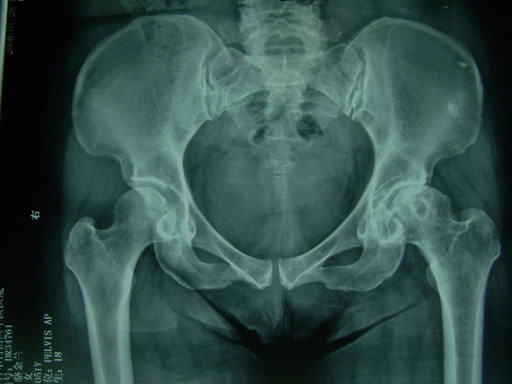

股骨头缺血性坏死关节活动障碍_主要为髋关节内旋和外旋不便。需要做哪些检查来确诊股骨头坏死?诊断股骨头缺血性坏死主要依靠体格检查和影像学检查,有时为了明确诊断,医生还会做病理学检查。

医生在询问病情之后首先会做体格检查,一般步骤为先按压胯骨周围,然后做“4”字试验,接着做髋关节活动度检查。可以对股骨头缺血性坏死作出初步的诊断。

股骨头坏死MRI的多样信号改变反映不同层面病变组织的代谢水平。股骨头缺血性坏死病因治疗是关键,必须减少负重,行走,忌蹦跳。